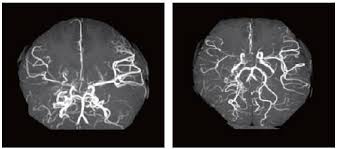

모야모야병은 뇌로 가는 주요 혈관이 점점 좁아지거나 막히는 질환입니다. 혈류가 감소하자 뇌는 이를 보상하기 위해 주변에 가느다란 새로운 혈관을 만들게 되는데, 이 혈관들이 뇌 영상에서 마치 연기처럼 보이기 때문에 일본어로 ‘모야모야’(희미한 연기)라는 이름이 붙었습니다.

◾ 직접 문합술 (Direct Bypass) : 외부의 혈관(두피 동맥)을 뇌혈관과 직접 연결하며 성인에게 주로 시행합니다.

◾ 간접 문합술 (Indirect Bypass) : 근육, 피하지방 등을 뇌에 붙여 혈관 신생 유도하며 소아에게 주로 시행합니다.

▶ 뇌로 가는 혈류를 회복시키고, 장기적인 합병증을 줄이는 데 매우 효과적입니다.

◾ 정기적인 MRI, MRA 등 뇌 영상 검사 필수